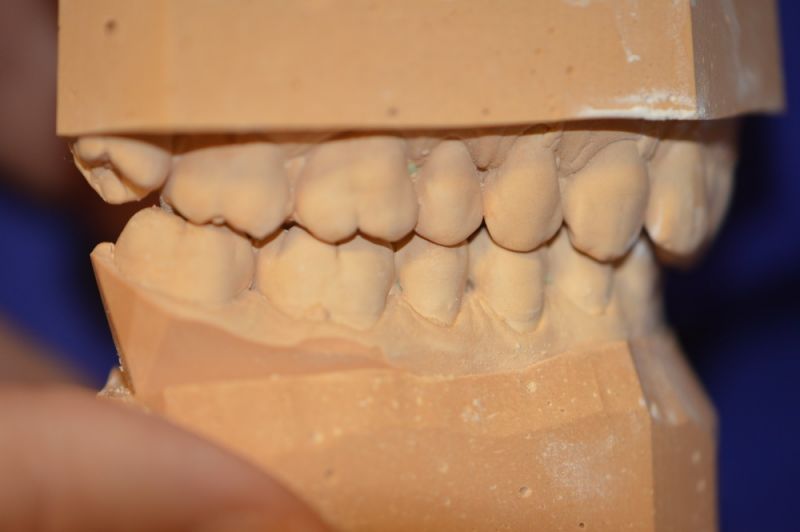

Es läuft dfas Nachweisverfahren einer CMD unter Einsatz eines adjustierten Aufbissbehelfs.

Deutlich erkennbar die Nonokklusion in neuromuskulär zenmtrierter Bisslage